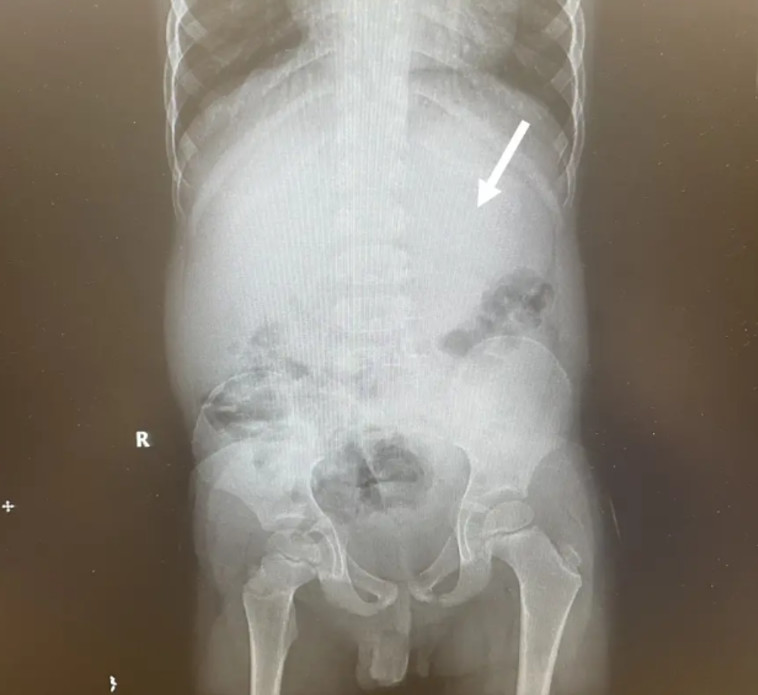

ילד שלעס עשרות מסטיקים ובלע את כולם באותו היום, גרם לעצמו לצרה צרורה והחל לסבול מכאבי בטן עזים ומשלשולים. הוא פונה בדחיפות לבית החולים, שם גילו הצוותים כי בבטנו ישנו גוש גומי החוסם את מעיו

40 מסטיקים חסמו את מערכת העיכול של הקטין

הרופאים שלפו את אוסף המסטיקים מבטנו של הצעיר באמצעות שימוש במלקחיים וצינורית מתכת והחולה סבל מכאבי גרון עקב ההסרה החודרנית שבוצעה בו במטרה לחלץ את גוש הגומי. בסופו של דבר הוא שוחרר ללא השלכות ארוכות טווח, כך על פי הדיווחים.

בעוד שדעות לא פופולריות הזהירו כי מסטיק עלול להישאר בגופנו במשך שבע שנים, מומחים הפריכו את האמונה הרווחת. "אם בלעת חתיכת מסטיק, היא תצא החוצה לאחר כ-40 שעות", אמרה הדיאטנית בת' צ'רווני לקליבלנד קליניק בשנה שעברה. "מכיוון שגומי לעיסה אינו ניתן לעיכול, הוא יוצא שלם. אך אם תבלעו כמה מסטיקים, הדבר עלול לגרום לחסימת מעיים, אז לא מומלץ לעשות זאת".